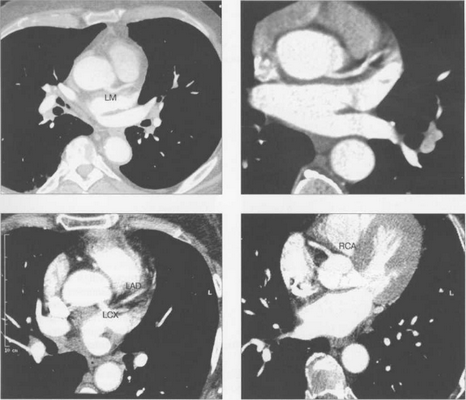

МСКТ в условиях внутривенного болюсного контрастирования позволяет визуализировать коронарные артерии (МСКТ-коронарография). Анализ состояния коронарных артерий выполняется сначала на аксиальных срезах (рис. 9.35). В постпроцессинговой обработке изображений используются различные виды реконструкций: многоплоскостные реформации (MPR), проекция максимальной интенсивности (MIP), трехмерные (VRT) (рис. 9.36).

Рис. 9.35. МСКТ-коронарограммы. Поперечные срезы.

Здесь и на рис. 9.36:

LM — ствол левой коронарной артерии, LAD — левая передняя нисходящая артерия, LCX — левая огибающая артерия, RCA — правая коронарная артерия.

Рис. 9.36. МСКТ-коронарограммы.

а, б — VRT-реконструкции; в — проекция максимальной интенсивности; г — многоплоскостная реформация.